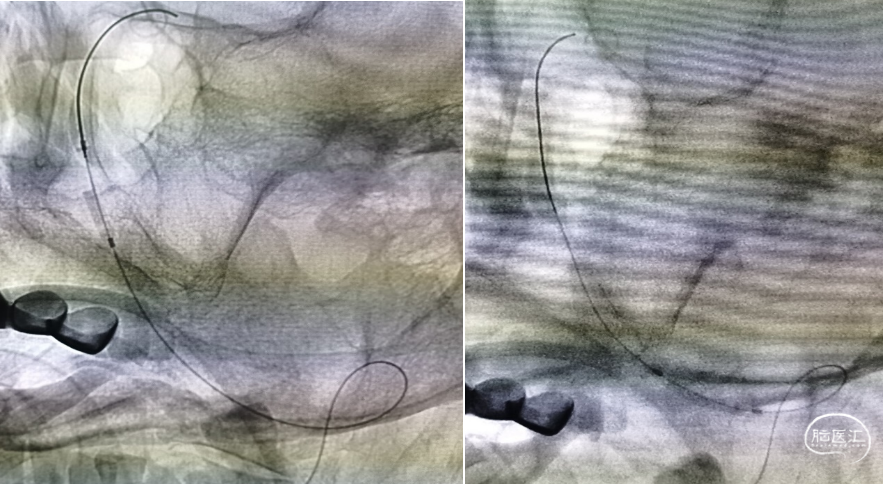

三型弓,最终采用泥鳅导丝、4F MPA1、6F Envoy同轴技术送入左侧椎动脉

Transcend携带SL-10微导丝进入左侧大脑后动脉,明确真腔内后交换Gateway2.0mm×15mm以命名压缓慢进行两次扩张,造影见现在较前改善,动脉瘤近端存在狭窄暂时未扩张

首先尝试并行式支架释放,但ProwlerPlus通过后SL-10无法进入动脉瘤内,考虑动脉瘤近端狭窄较重,考虑患者血管情况较差,未尝试强行通过,遂考虑穿支架网眼。尽管选择的是4.5 mm×37 mm的EP支架,但长度仍然捉襟见肘,头端尝试释放于基底动脉时末端距离不足,考虑椎基底交界处血管扩张情况尚满意,遂将支架释放于椎动脉